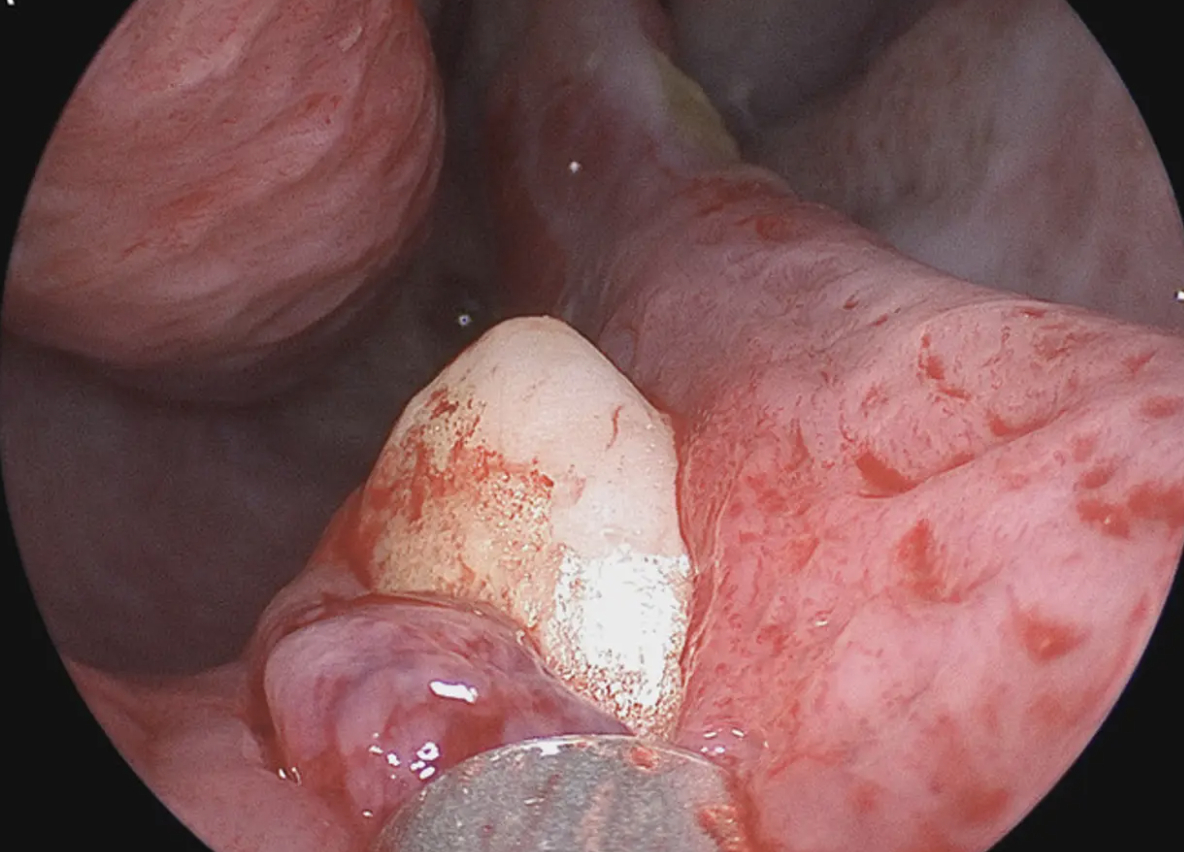

“Rhinoskopien viste en hård, ikke-øm, hvid masse i højre næsebor,” skriver Sagar Khanna og Michael Turner wrote i The New England Journal of Medicine.

“Tanden blev fjernet under oral og otolaryngologisk kirurgi ved hjælp af en intranasal tilgang. Tanden målte 14 mm i længden, og der var ingen postoperative komplikationer.”